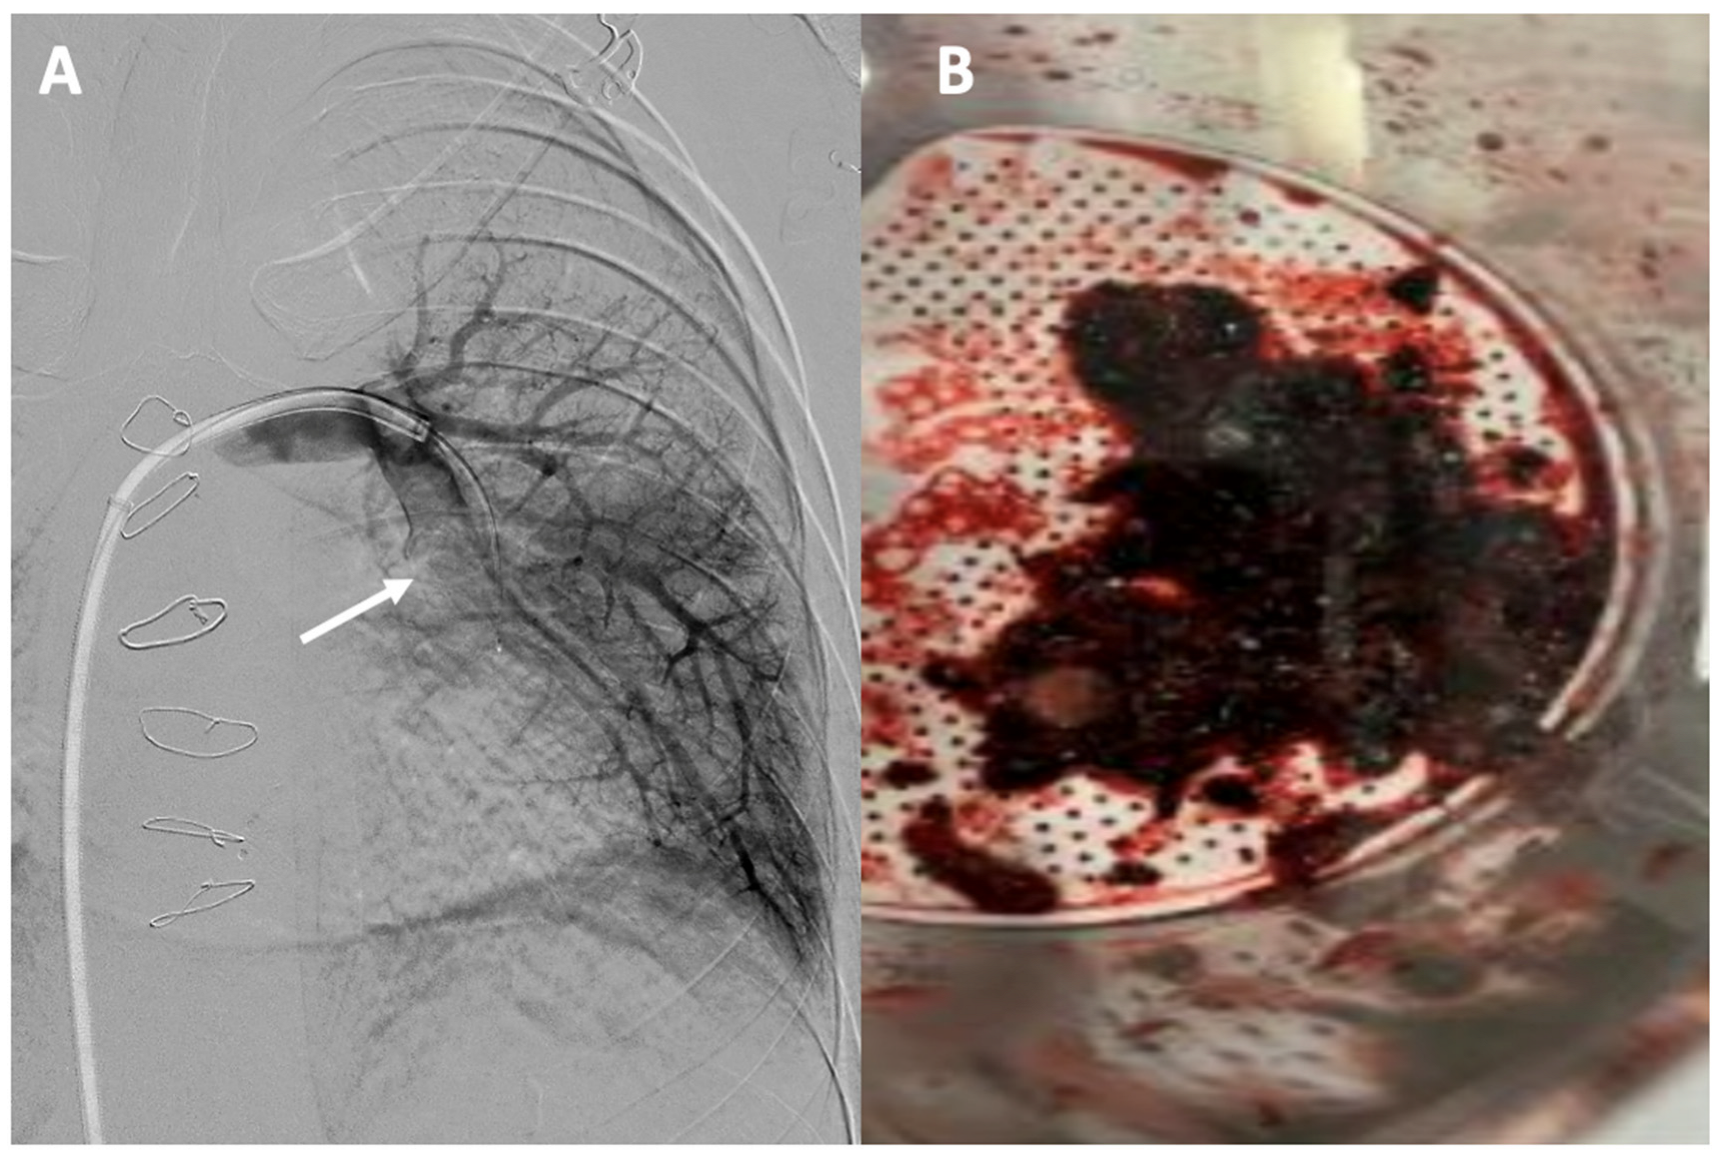

Figure 6.

Acute pulmonary thromboembolism: (A) angiographic image of a thrombotic occlusion in the main branch of the left lower lobar artery (see arrow); (B) thrombus extracted after percutaneous aspiration thrombectomy.

Adult Fontan patients face a significant risk of thromboembolic complications [95]. One of the primary limitations lies in diagnosis as well as risk stratification. Conventional methods such as electrocardiography, echocardiography, and changes in troponin levels are less useful due to the absence of a right ventricle. The use of computed tomography angiography for the initial diagnosis of pulmonary embolism in patients with Fontan circulation is essential but often presents challenges [96]. Defects in contrast filling due to alterations in the venous phase are caused by the lack of connection between the right ventricle and the lung, as well as the typical asymmetry in pulmonary flows. Therefore, it is necessary to consider different strategies when acquiring images, such as using a dual contrast injection in both the upper and lower extremities and obtaining biphasic images to facilitate pulmonary opacification [97,98]. Various percutaneous options have been developed for the treatment of pulmonary embolism based on techniques such as mechanical thrombectomy, aspiration thrombectomy, and catheter-directed thrombolysis [99]. Although the indications for such therapies in this population are not clearly defined, there have been satisfactory cases of thromboaspiration in Fontan patients [100] (Figure 6).